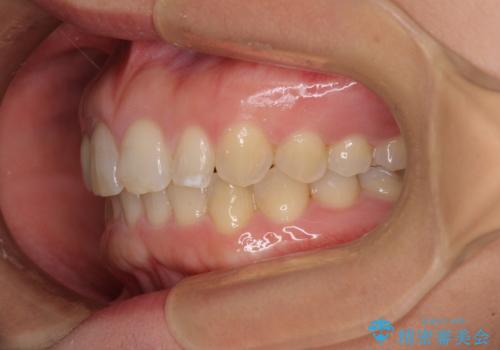

前歯の歯並びと小さい歯を改善 インビザラインとオールセラミッククラウン

- 前歯の空隙と矮小歯を気にして来院された患者様です。

上下の歯列不正はインビザラインにより整えることとしました。

矯正治療の後に、前歯1歯と奥歯をオールセラミックにて治療することとしました。

矯正治療により矮小歯前後にスペースを作りながら歯列を整え、セラミッククラウン装着後に最終的に歯列と咬合を仕上げました。